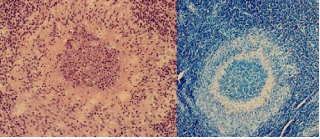

Patient’s clinical course was unusual since after initial presentation and patient several times repeatedly developed the same symptoms. Patient was admitted within 6 months in total 4 times in the ward because of dysphagia, sore throat and subjective shortness of breath. There was no stridor at any point. Fever was present at the time of first and third admission. Since swelling of epiglottis and lingual tonsil were present, patient received high doses of corticosteroids intravenously and per os. There was no swelling of the vocal cords at any point and airway was patent. Each admission lasts between 4 to 7 days. CRP was elevated every time that patient was admitted. Leukocytosis was present during the first, third and fourth admission of the patient. Since patient had fever and inflammation parameters were elevated, patient received in total two courses of intravenous antibiotics and five courses of antibiotics per os. Along with a follow-up appointment between the second and third admission, a neck MRI was taken and it revealed a hypertrophy of lingual tonsil and neck lymphadenopathy. During the third admission of the patient in the hospital, patient complained also for tenderness to her ankles. A thorax x-ray showed no pulmonary infiltrates but visualization of the bronchus close to the hilum of the lung was prominent. During the admission, patient’s dysphagia and airway symptoms were more prominent. Thus, different laboratory tests were carried out to exclude diseases such as sarcoidosis and vasculitis. A computed tomography (CT) body scan was ordered. CT imaging showed one solitary condensed triangularshaped 6-mm shadow in right lung (in the middle lobe). In the left ovary, there was a 2.8 cm x 4 cm cyst. In SI-joints, there was some mild sclerosis. No pathological lymphadenopathy was found. Three days later, a biopsy was taken from the lingual tonsil. Histopathological examination of lingual tonsil, revealed the presence of necrotizing granulomatous inflammation (non caseating granulomas with giant cells). There was no evidence of sarcoidosis and tuberculosis was excluded figure 1.

Magnetic resonance imaging revealed hyperthophy of the lingual tonsil neck lymphadenopathy.

Figure 1: Magnetic resonance imaging revealed hyperthophy of the lingual tonsil neck lymphadenopathy.

Pathological examination of the lingual tonsil showed noncaseating necrotizing granulomatous inflammations.

Figure 3: Pathological examination of the lingual tonsil showed noncaseating necrotizing granulomatous inflammations.